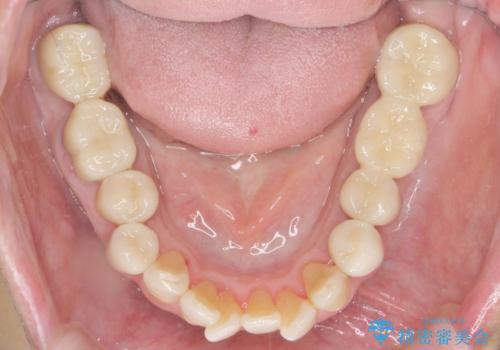

- 見た目の悪い銀歯や虫歯、歯の欠損、全体的な治療を希望されて来院されました。

インプラント治療や根管治療・セラミック治療を総合的に考えた精度の高い治療を計画し、しっかり噛めるようになるのはもちろん長期的な予後や審美性の向上を考えた全顎的な治療を実践していきます。

期間は約2年ほどかかりましたが、審美的な仕上がりとともに清掃のしやすさも非常に満足いただくことができました。